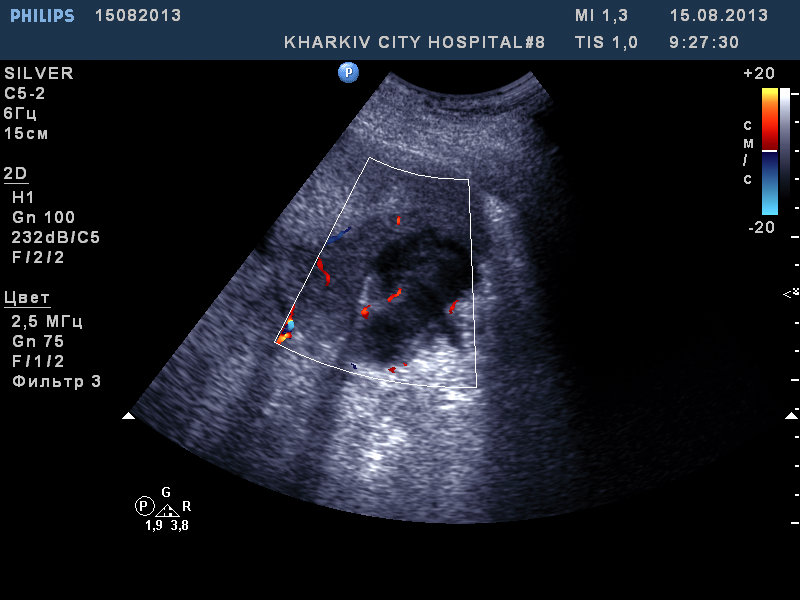

Пациент 63 лет. доставлен в клинику с фибр.предсердий. Ритм восстановили. Температура до 40 (свечками). сОЭ 60 .Жалобы на тупую разлитую боль в правом подреберье.

При проведении узи:

Желчный пузырь типично расположен, деформирован, неровный нечеткий контур. Неоднородное содержимое. Конкремент в полости не лоцируется. У желчного пузыря множественные гипоэхогенные участки неровной формы с наличием жидкостного компонента.

Расцениваю как признаки острого холецистита, признаки перфорации желчного пузыря, признаки подпеченочного абсцесса. Нельзя исключить холедохолитиаз.

Соглашусь, похоже на острый деструктивный холецистит, паравезикальный абсцесс. Четко видна дыра в стенке пузыря.

Кстати, не вижу камней в пузыре, - как вариант - деструкция/некроз ж. пузыря вследствие тромбоза пузырной артерии, подпеченочный абсцесс.